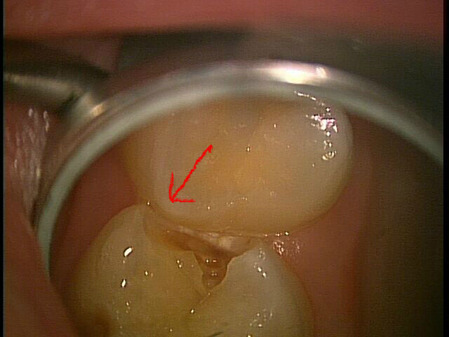

この写真は乳歯が虫歯になっているんだけど。。。隣のノーマルな歯が押してきているように感じるのは私だけでしょうか?

このやじるの先のあたり、歯が虫歯で崩壊して歯質がないのを良い事に、グイグイ押している気がしない?つまり、1つはグイグイ押してくるから歯質に影響して虫歯になった可能性と、グイグイ押しているからこのままいくとやや倒れて本来の位置よりもずれる可能性があるって事。いや〜難しい。

そう私はこれを見て、本当人間の体って良くできてるなーと思うのは、乳歯が吸収するのにも意味とがタイミングがあって生態が決めているって事。もし虫歯じゃなかったら隣の永久歯のポジションはちょっと違ったポジションになったと思う。

そして、もしこの歯を治療するとするならば、隣に食い込んでしまった分どうするか?という事もあるし充填する形態も変える必要があるのかもしれない。

それは今後の見通しとどう歯列を導いていくのかによるので、決まった答えはない。